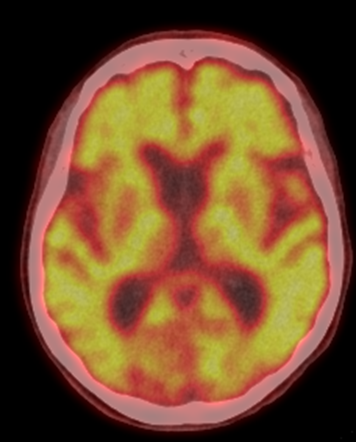

this image is an example of axial PET, CT or fused

axial fused

what is the organ of this image

brain

what is view of this image

transaxial (transverse) slice

what are the results of the scan

brain metastases